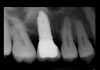

Fig 19. Peri-apical X-ray 13 months after sinus floor elevation and implant insertion.

Figure 19